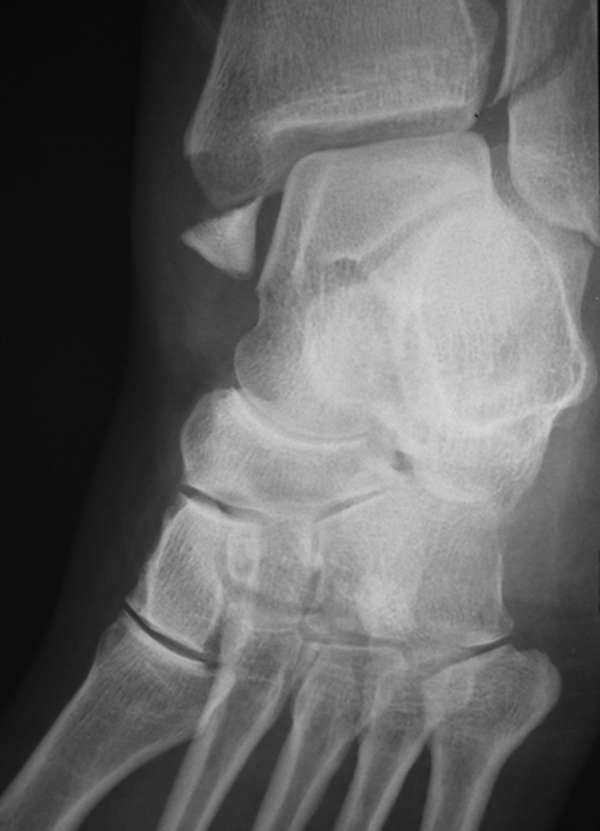

Hỏi bệnh sử và khám thực thể. Chụp X-quang và các kiểm tra hình ảnh khác sẽ được thực hiện.

Chụp cắt lớp vi tính (CT Scan), chụp cộng hưởng từ (MRI), chụp X-quang.